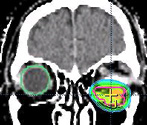

典型的な三叉神経痛の場合、約90%で除痛効果が得られます。特に高齢者や手術後に痛みが再発した患者さんには良い治療法です。三叉神経が脳幹に入る部位(赤丸で示す)を照射します。

治療計画の作成画像

医学物理士による精度検証画像 -